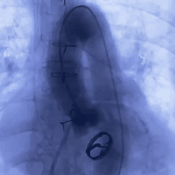

主动脉根部造影

20mm球囊预扩张

瓣膜缓慢释放

瓣膜释放后造影评估